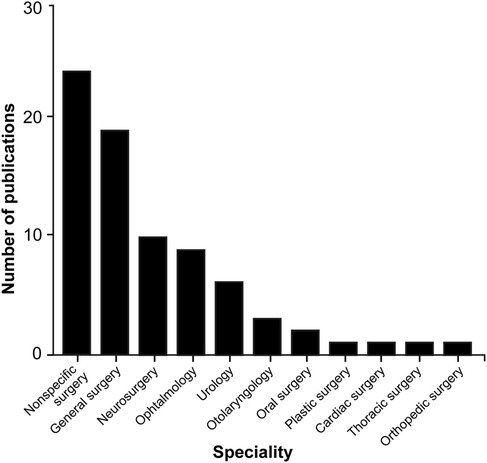

Examining the different functional sensors used in ML applications within surgical practice reveals a lack of uniformity, with a wide range of sensors being used. However, image datasets (n = 7), videos (n = 29), and camera recordings (n = 21) are among the main systems used to collect information or train the algorithms (Table 2). ML algorithms are most extensively studied in general surgery (n = 19), neurosurgery (n = 10), and ophthalmology (n = 9), but their applications are used in a broad spectrum of surgical specialties (Table 2; Figure 4).

Figure 4. Bar chart showing the surgical fields in which machine learning (ML) algorithms are most commonly applied through hand and instrument tracking methods. As illustrated in the chart, the use of ML algorithms in hand and instrument tracking methods is most widespread in general surgery, neurosurgery, and ophthalmology. However, research has also begun in various surgical fields, including oral surgery, orthopedics, plastic surgery, otolaryngology, urology, cardiac surgery, and thoracic surgery. The nonspecific surgery group includes studies focused on surgical simulation training, hand pose estimation, suturing, knot tying, and basic laparoscopic and endoscopic training, which do not belong to any particular surgical field. Used with permission from Barrow Neurological Institute, Phoenix, Arizona.